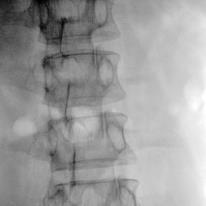

We present a novel deep learning-based framework: Embedded Feature Similarity Optimization with Specific Parameter Initialization (SOPI) for 2D/3D registration which is a most challenging problem due to the difficulty such as dimensional mismatch, heavy computation load and lack of golden evaluating standard. The framework we designed includes a parameter specification module to efficiently choose initialization pose parameter and a fine-registration network to align images. The proposed framework takes extracting multi-scale features into consideration using a novel composite connection encoder with special training techniques. The method is compared with both learning-based methods and optimization-based methods to further evaluate the performance. Our experiments demonstrate that the method in this paper has improved the registration performance, and thereby outperforms the existing methods in terms of accuracy and running time. We also show the potential of the proposed method as an initial pose estimator.